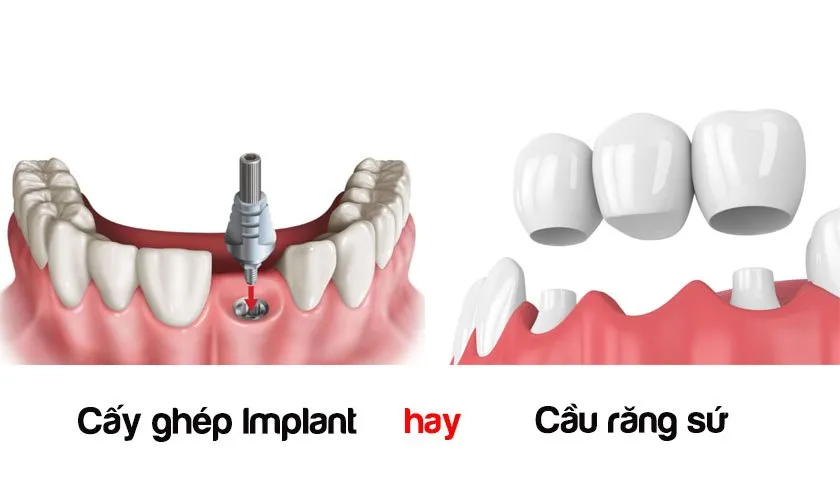

Mất răng ảnh hưởng tới sức khỏe răng miệng, chức năng nhai cũng như khiến bạn trở nên tự ti với nụ cười. Lúc này,có hai giải

Trồng răng implant là phương pháp phục hồi răng hiệu quả nhất hiện nay. Phương pháp này sẽ thay thế những chiếc răng hỏng hoặc mất mà